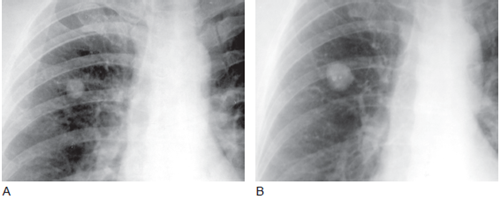

图4 生长的错构瘤

A. 胸片显示上叶边界清楚,直径约1cm 的结节;B.3 年之后,结节直径达2cm,结节内可见几个钙化灶,结节倍增时间是1 年